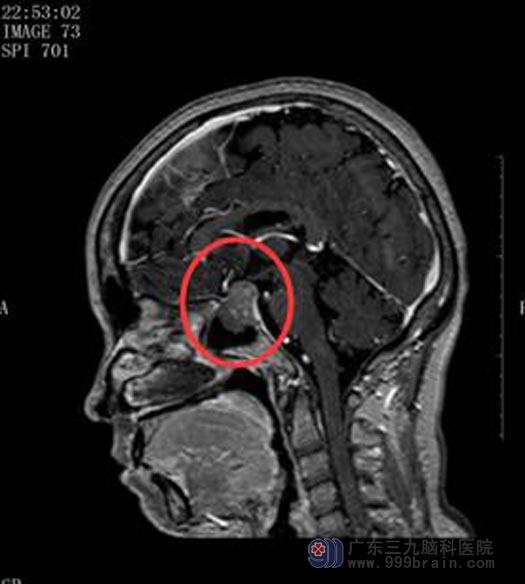

在广东三九脑科医院垂体瘤诊疗中心,谭女士做了更详细的检查,MRI显示T低密度等信号影,T2高密度等信号影,右侧有囊性病变。参考各项检查结果以及明显的内分泌异常表现,垂体腺瘤的诊断明确。经谭女士和家属同意后,决定经鼻蝶入路切除垂体瘤。

手术前